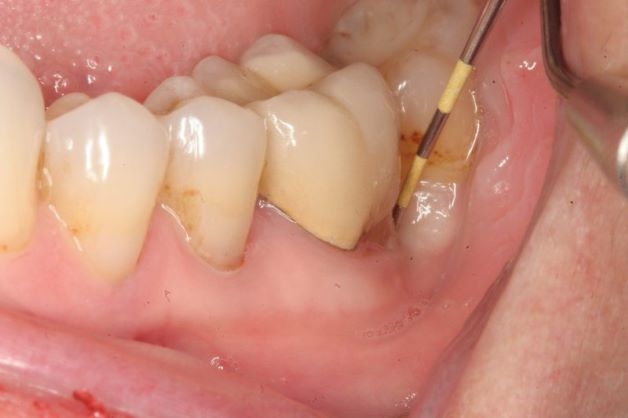

Viêm cuống răng là bệnh lý về răng miệng phổ biến và gây đau đớn, ảnh hưởng đến sinh hoạt và sinh hoạt của người bệnh

– Khi bị viêm quanh cuống răng, người bệnh thường có các biểu hiện như: mệt mỏi, sốt cao trên 38 độ C, kèm theo đó là các dấu hiệu nhiễm khuẩn như: môi khô, lưỡi bẩn, cũng có những trường hợp người bệnh có hạch ở vùng dưới hàm hoặc cằm.

– Đau nhức răng: Lúc này các cơn đau thường liên tục, nghiêm trọng hơn còn lan lên nửa đầu. Mức độ của cơn đau tăng lên khi nhai thức ăn và không có dấu hiệu thuyên giảm nếu người bệnh không dùng thuốc giảm đau. Bệnh nhân cũng có thể xác định được vị trí răng bị đau, đây là nguyên nhân khiến người bệnh bỏ ăn, lười ăn và không dám nhai khi ăn.

– Vùng da ngoài tương ứng vị trí tổn thương sẽ sưng nặng nề, đỏ đau, ấn vào thấy đau, có hạch.

– Răng đổi màu hoặc có thể không đổi màu, lúc thăm khám thường sẽ thấy các tổn thương do sâu răng hoặc răng đã được điều trị hoặc những tổn thương khác mà không phải do sâu.

– Dấu hiệu của viêm quanh cuống răng điển hình là khi gõ dọc vào răng người bệnh sẽ đau dữ dội so với khi gõ ngang.

– Niêm mạc tại ngách lợi tương ứng vùng cuống răng cũng bị đỏ, sưng nề, mô lỏng lẻo.